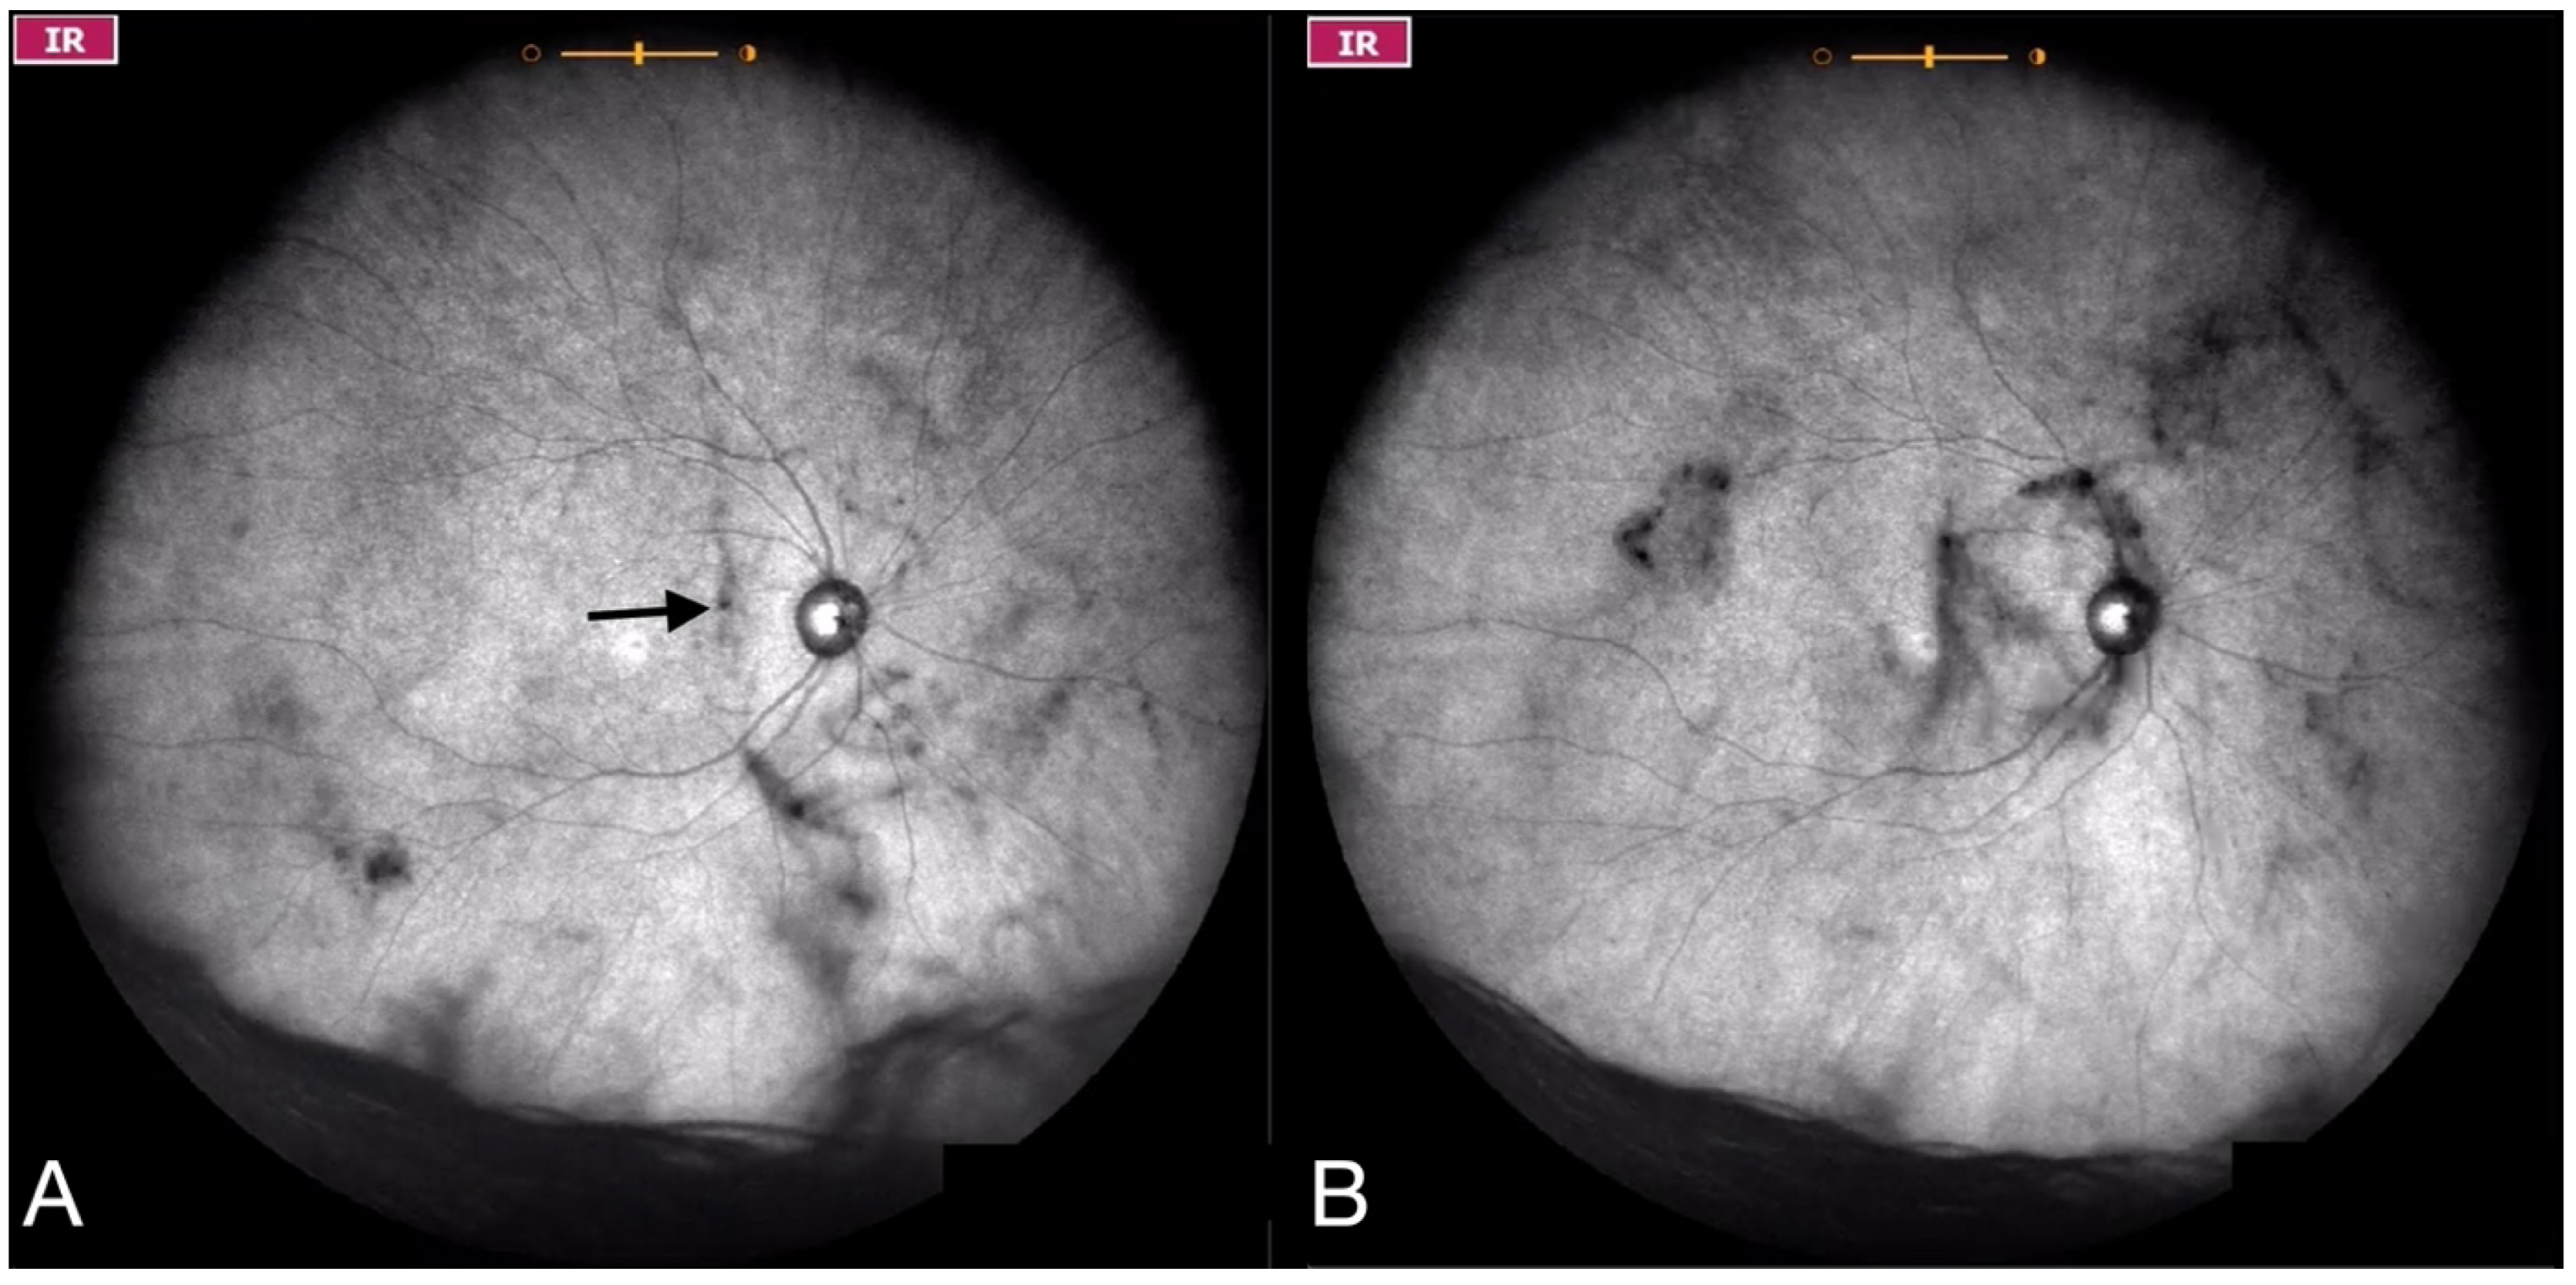

| Grade 2—Diffuse opacities that cross the center of the macula (Figure 3 and Video S3) and/or dense opacities that do not cross the center of the macula (Figure 4 and Video S4). |

| Grade 3—Dense opacities outside the center of the macula in primary gaze, that cross the center of the macula with eye movement (Figure 5 and Video S5). |